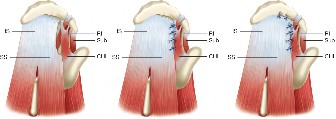

It should be noted that reverse total shoulder arthroplasty is also the procedure of choice in patients with cuff-tear arthropathy (aka rotator cuff arthropathy). Characteristics of cuff-tear arthropathy include superior migration of the humerus due to a massive rotator cuff tear, glenohumeral joint destruction, subchondral osteoporosis, and humeral head collapse (see Fig. 2–17). A reverse total shoulder

Figure 2–17_X-rays of a patient showing evidence of cuff tear arthropathy. The humerus is migrated superiorly, the glenohumeral joint is destroyed, there is subchondral osteoporosis, and the humeral head is collapsed. (From Ecklund KJ, Lee TQ, Tibone J, Gupta R. Rotator cuff tear arthropathy. _J Am Acad Orthop Surg. 2007;15(6):340–349.)